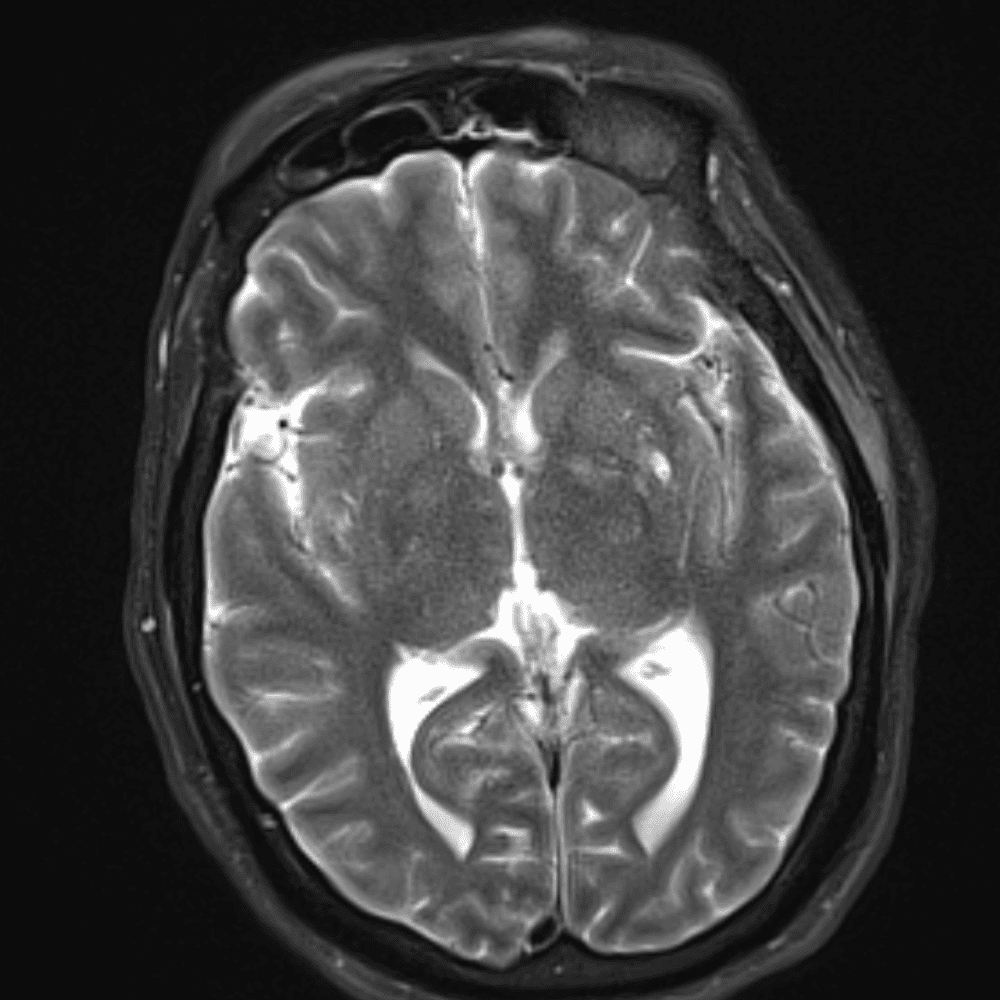

๋‹น์ง ์‹œ ํ”ํžˆ ๋ณผ ์ˆ˜ ์žˆ๋Š” ์‚ฌ๋ก€์˜ ์ „ํ˜•์ ์ธ ์˜ˆ๋ฅผ ํฌํ•จํ•ฉ๋‹ˆ๋‹ค.

39 ์‚ฌ๋ก€

์—ฐ์Šต

๋ฏธ๋ฌ˜ํ•˜๊ฑฐ๋‚˜ ์–ด๋ ค์šด ์‚ฌ๋ก€์™€ ์ผ๋ถ€ ์ •์ƒ ์‚ฌ๋ก€๋ฅผ ํฌํ•จํ•˜์—ฌ ๋‹น์ง์„ ์‹œ๋ฎฌ๋ ˆ์ด์…˜ํ•ฉ๋‹ˆ๋‹ค.

50 ์‚ฌ๋ก€